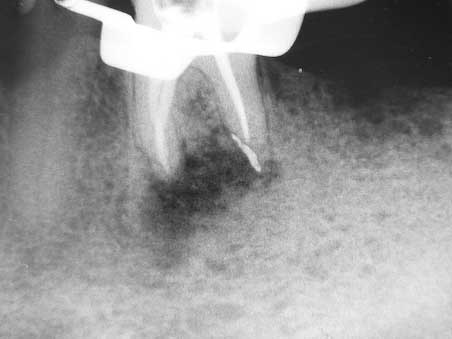

Apikale Aufhellung 001 Bild 4

Veröffentlicht 10. Februar 2009 am 452 × 339 in Apikale Aufhellung (1)